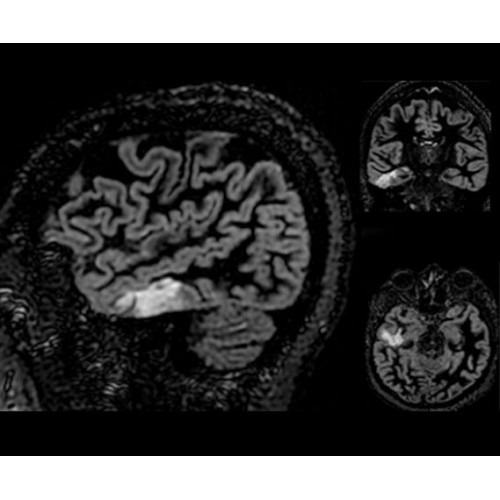

Система SIGNA PET/MR предлагает впечатляющие клинические возможности и открывает доступ к наиболее полным пакетам программных приложений.

• TurboTOF — инновационная технология позволяет корректировать коэффициент затухания сигнала и минимизировать потери анатомических данных, создавая МР-систему для количественной визуализации.

• Q.Clear — в основу технологии легли накопленные знания о том, как минимизировать помехи при реконструкции и получить четкое изображение. При значительном улучшении качества изображения сохраняется точность расчетов. Сочетание технологии TOF и реконструкции Q.Clear — ваш надежный помощник для получения точных и достоверных данных.

• МРТ с функцией нулевого времени эхо (ZTE) отличается точностью, возможностью персональных настроек и отсутствием ионизирующего излучения. Она приходит на смену традиционному исследованию на основе рентгеновского излучения. МРТ с функцией нулевого времени эхо (ZTE) на базе SIGNA ПЭТ/МРТ является более надежной и быстрой по сравнению с системами, использующими сверхмалое время эхо (UTE).

• Приложения для коррекции артефактов движения — используйте наиболее широкий набор инструментов, таких как PROPELLER, PROMO и навигаторы Pencil Beam, позволяющих снизить влияние непроизвольных или физиологических движений на качество изображений.

• Специальный пакет приложений для измерения и сравнения объемных изображений ЦНС с нормами поможет вам в диагностике нейродегенеративных заболеваний, а дополнительные инструменты визуализации — в постановке точного диагноза с помощью бета-амилоидов и радиоизотопных маркеров ФДГ.